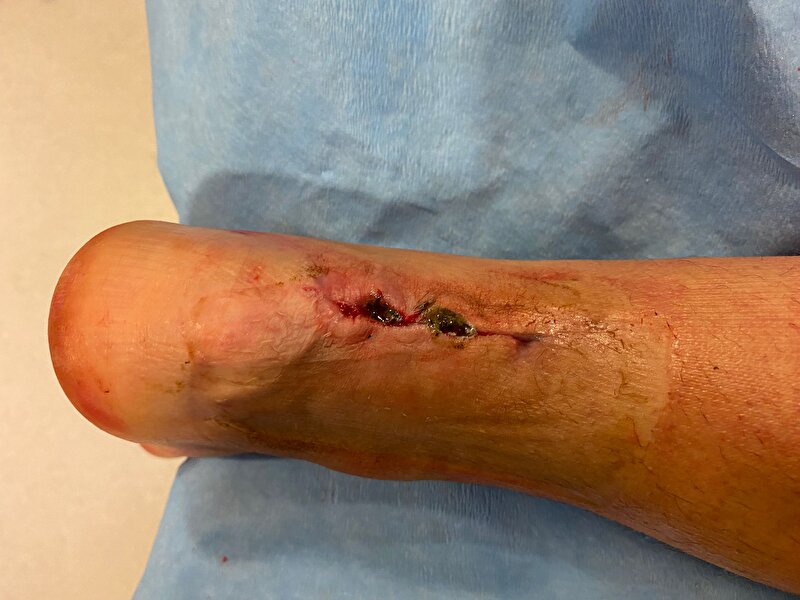

Na mijn vorige avontuur dat het wondvocht door het gips heen lekte, had ik vandaag weer controle. Had ergens het idee dat ik weer wat rook, maar zag verder niks dit keer. Zou eigenlijk loopgips gaan krijgen vandaag, maar zat er helaas nog niet in ivm de wond. Heb een bacterie te pakken die resistent is voor antibiotica. Wond geneest niet goed, hij was nog 1,5cm diep en littekenweefsel vormt niet goed.

Even in spoiler hoe hij onder gips vandaan kwamHet groenige is kennelijk kenmerkend voor die bacterie.